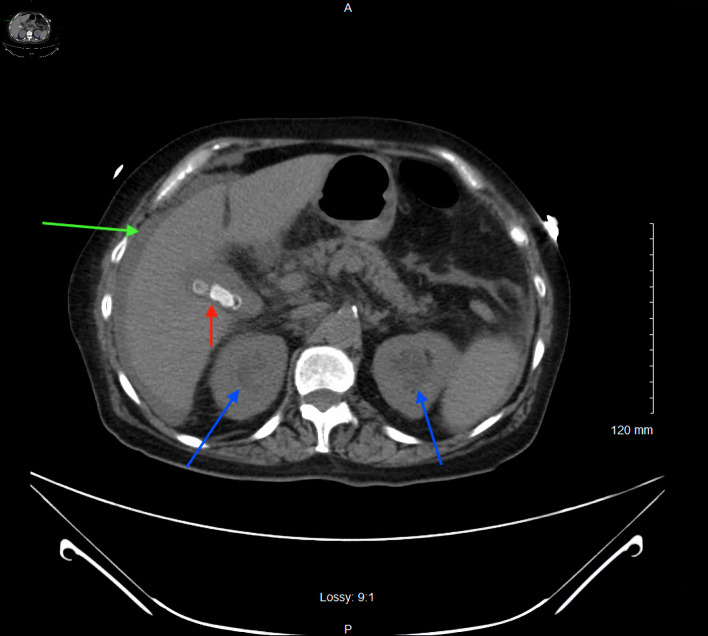

Abstract Image